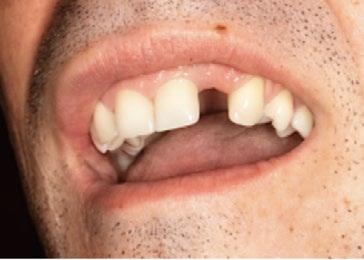

En 1987 y a pesar de que las rehabilitaciones unitarias no ferulizadas eran aún consideradas experimentales, tratamos a dos pacientes jóvenes no fumadores que habían perdido un solo diente.

En la literatura científica, los dos primeros artículos que describen implantes unitarios —es decir, no ferulizados a otros implantes— se publicaron en 1986:

2. T. Jemt, en el Journal of Prosthetic Dentistry, publicó por primera vez en 1986 la descripción de la sustitución de dientes unitarios mediante implantes osteointegrados en pacientes parcialmente edéntulos. (Figura 3)

El primero de nuestros pacientes, de 32 años, había perdido su incisivo central superior derecho a los 12 años y el segundo, de 29 años, había perdido su incisivo lateral superior izquierdo en un accidente de tráfico ocurrido siete años antes. (Figura 4)